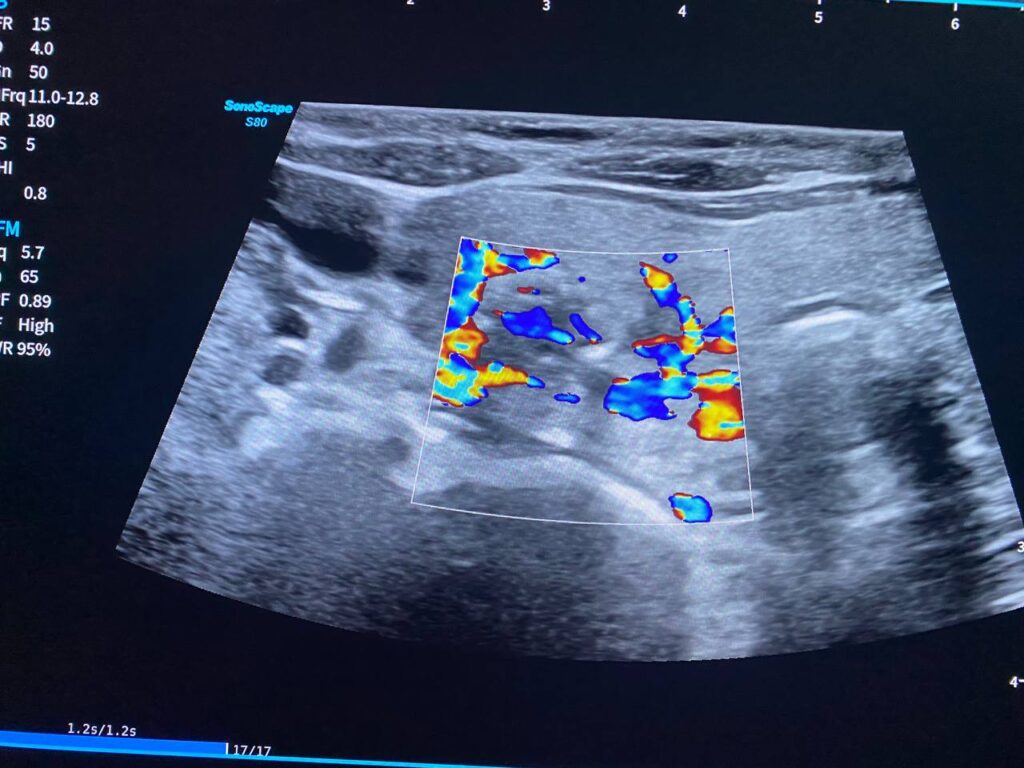

Right lobe size = 31x57x25mm, normal in texture, contain heterogenous circumscribed nodule 33x18mm, contain macrocalcification , mostly benign , TIRADS 3 , For short interval follow up

Left lobe size = 21.4x48x14mm, normal in texture, contain heterogenous circumscribed nodule 15.4×9.6mm , TIRADS 3 , and other nodule 10.8x5mm , contain micro calcification , TIRADS 3 , For short interval follow up